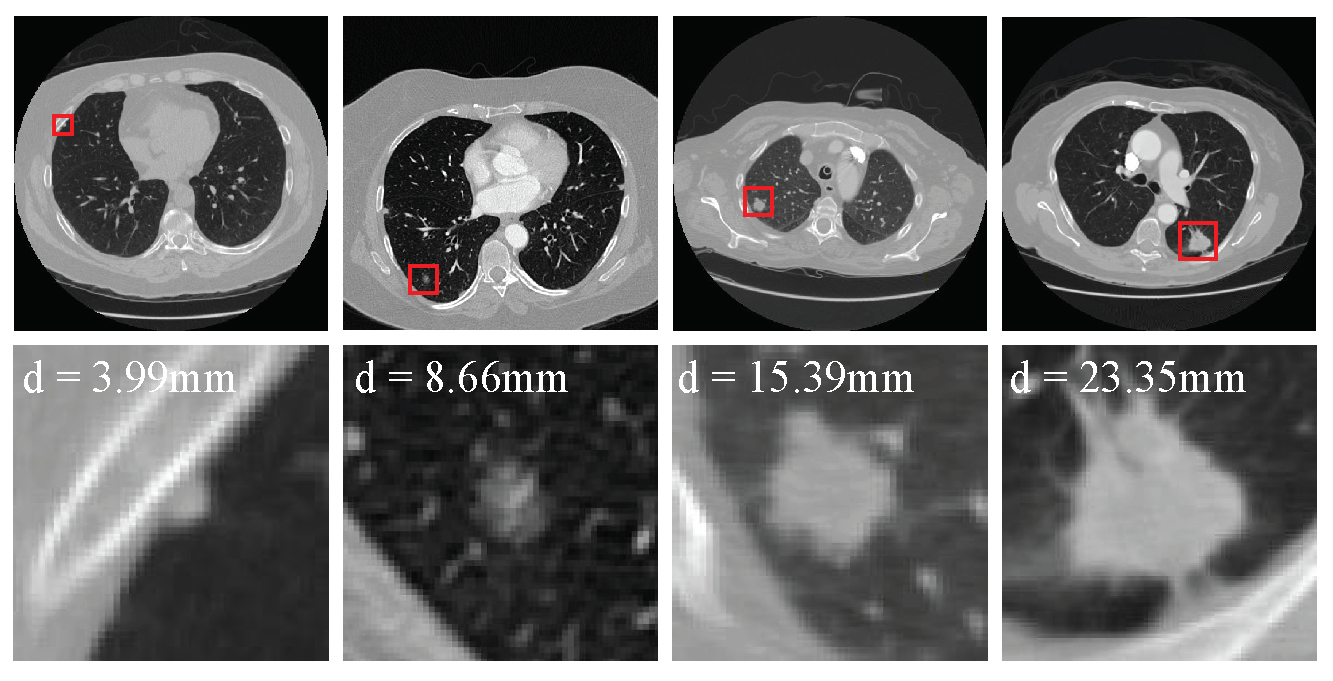

5.1. Effect of Nodule Size on Detection